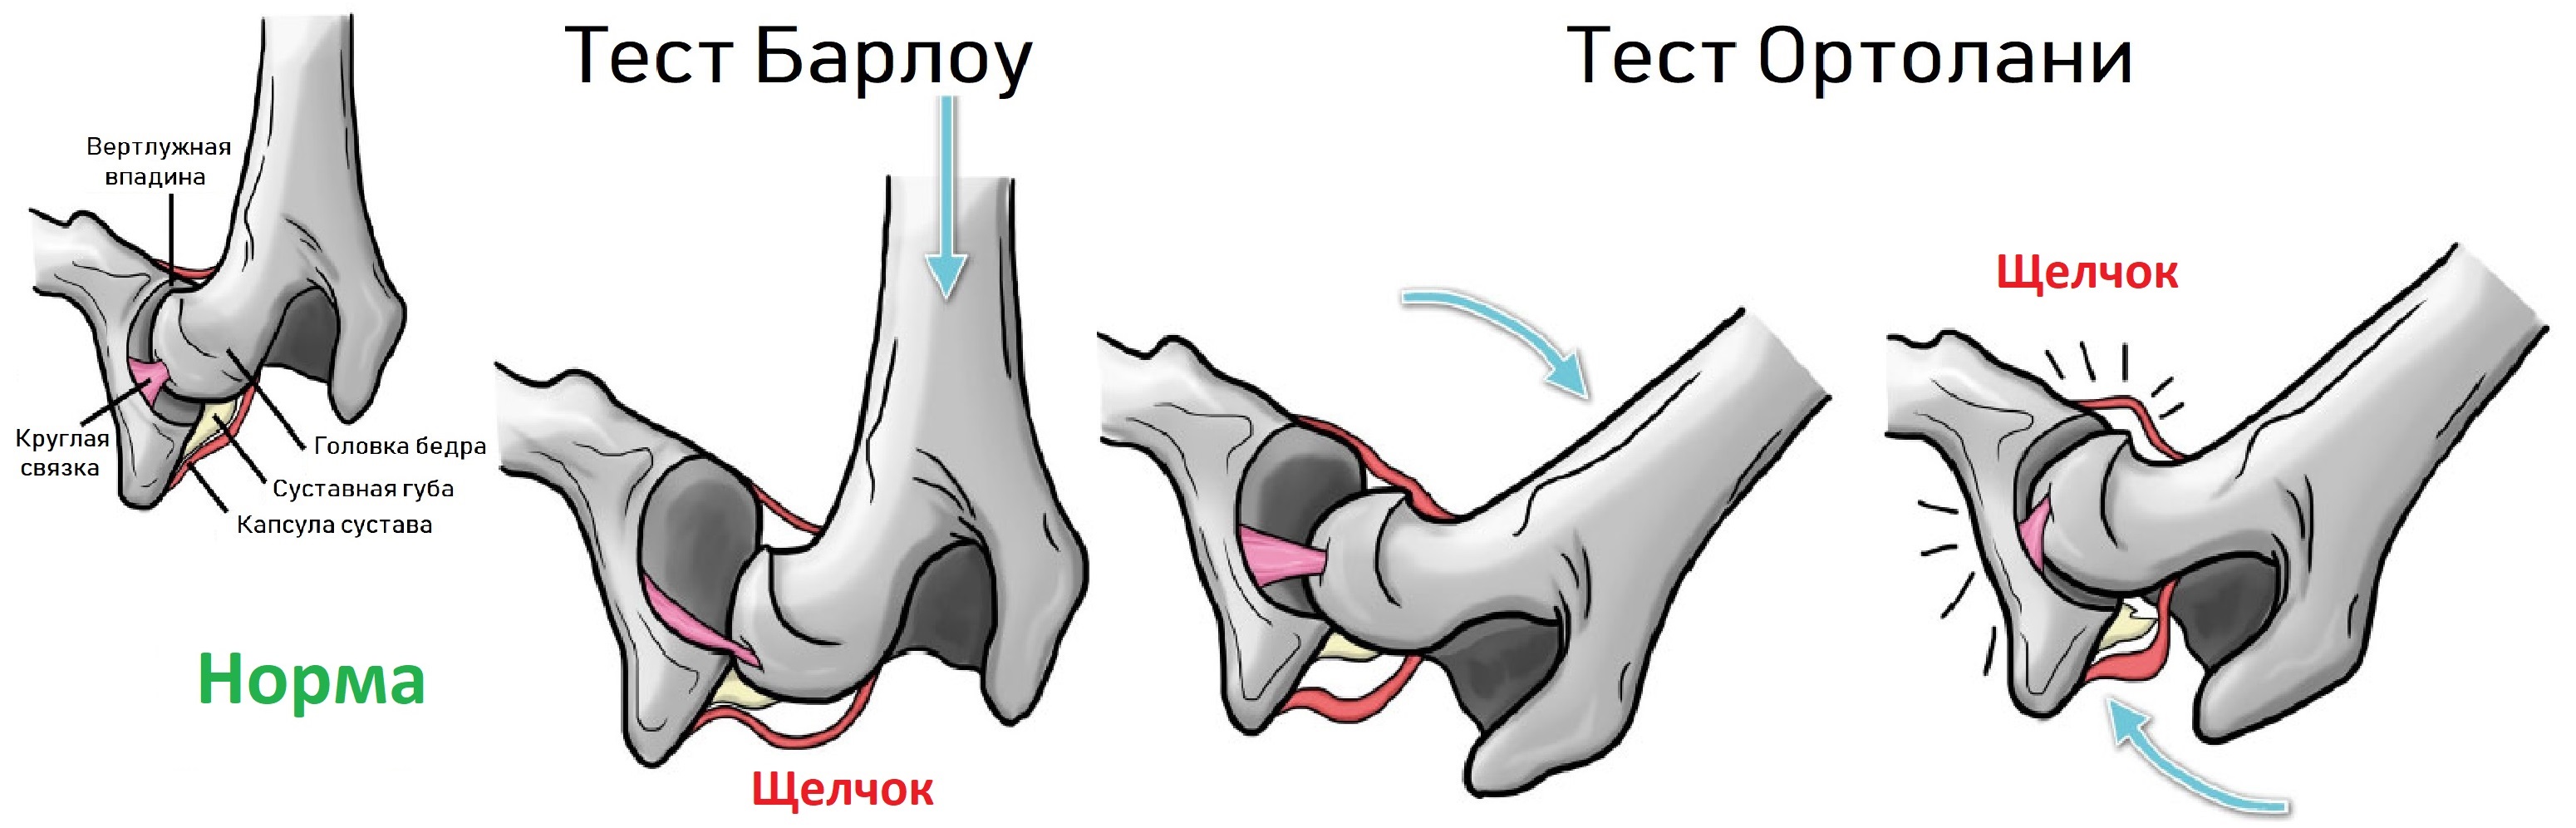

Оссификация тазобедренных суставов: что это и как проявляется?